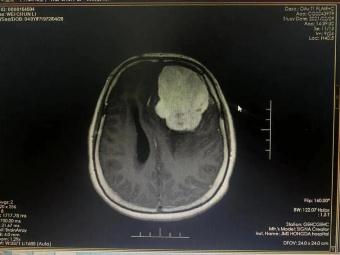

手術(shù)前 手術(shù)后

術(shù)前神經(jīng)外科與麻醉科、手術(shù)室、輸血科等科室反復(fù)認(rèn)真研究,制定了精細(xì)的手術(shù)方案和應(yīng)急預(yù)案。2月23日手術(shù)如期進(jìn)行并成功順利完成。術(shù)后第一日,患者神志清、言語明,對答問題流利切題;查體配合,右側(cè)肢體肌力明顯增強(qiáng),生命指征平穩(wěn)。術(shù)后在神經(jīng)外科護(hù)理團(tuán)隊的精心護(hù)理下,患者恢復(fù)良好,可正常離床活動,目前已經(jīng)康復(fù)出院。